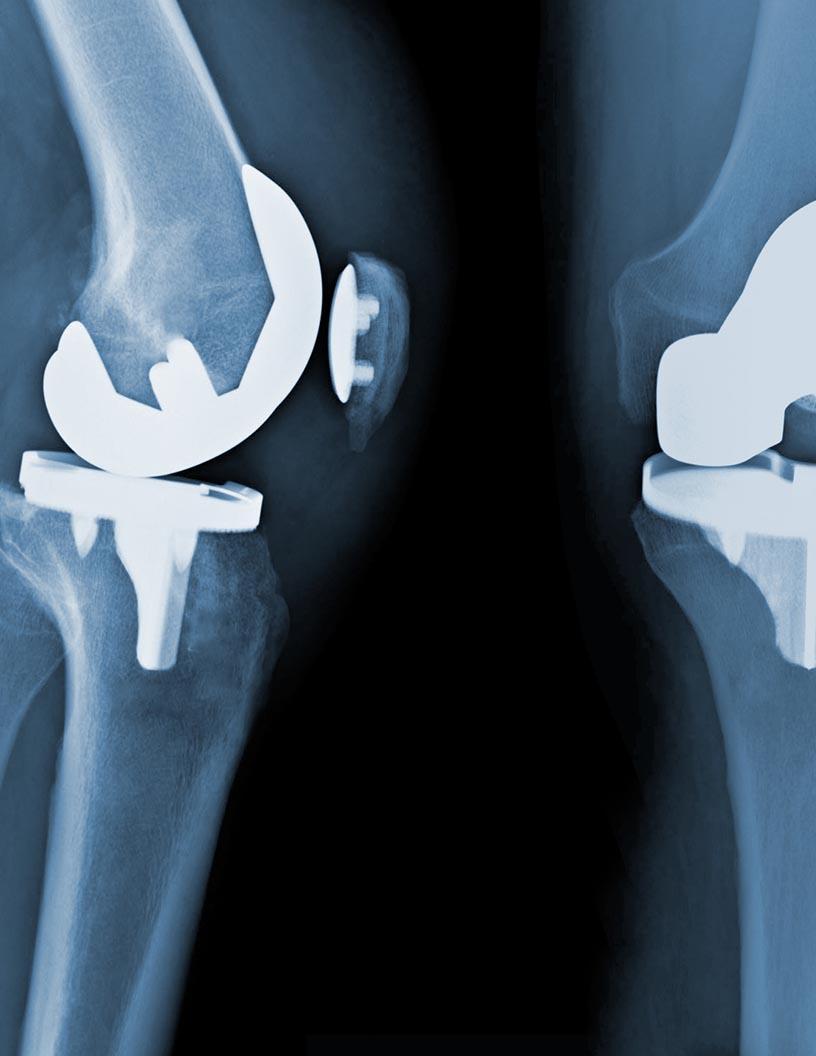

The Digit Joint Implants Market is experiencing significant growth, driven by rising cases of osteoarthritis and rheumatoid arthritis affecting the fingers, toes, and small joints. Common implant types include MCP joint implants, PIP joint implants, MTP joint implants, and trapeziometacarpal implants, as well as specialized products like toe implants, metacarpal joint implants, and metatarsal joint implants. These orthopedic digit implants are used in arthroplasty implants procedures to restore joint mobility, improve hand and foot function, and relieve chronic pain. Innovations such as 3D printed implants, custom digit implants, and computer-aided implants are enhancing outcomes through tailored fits and faster recovery times. The demand for minimally invasive implants that support bone preservation and articular cartilage restoration is on the rise, especially for conditions like hallux rigidus.

Material advancements are central to the performance of digit joint implants. Key implant materials include pyrocarbon implants, titanium implants, nitinol implants, cobalt chrome implants, polyethylene implants, biodegradable implants, and silicone implants, all selected for their biocompatible properties and durable construction. Devices such as intramedullary digit implants, flexible intramedullary implants, hemi phalangeal implants, and Morse taper implants offer enhanced anatomical compatibility, especially in finger joint implants and toe HemiCAP implants. These joint replacement implants help achieve a balance between mechanical strength and flexibility, critical for long-term success in active individuals. Additionally, custom prosthetic digits and stable construction implants are playing an increasingly important role in both trauma care and degenerative joint disease management

Research Analysis Overview

Growing interest in joint restoration implants and biomechanics implants is reshaping clinical approaches to hand joint implants and foot joint implants. Surgeons now seek advanced biomaterials and one-piece implants that reduce failure risks and improve functional restoration. Devices aimed at the scaphoid bone, digit, and phalangeal joints are being refined with joint mobility implants and osteointegrative properties for long-term success. Technologies like computer-aided implants and custom digit implants are helping deliver precision treatment in orthopedic procedures. Moreover, the integration of smart surgical planning tools is contributing to better implant alignment and faster post-operative rehabilitation, especially in patients requiring joint replacement implants for degenerative or traumatic conditions.